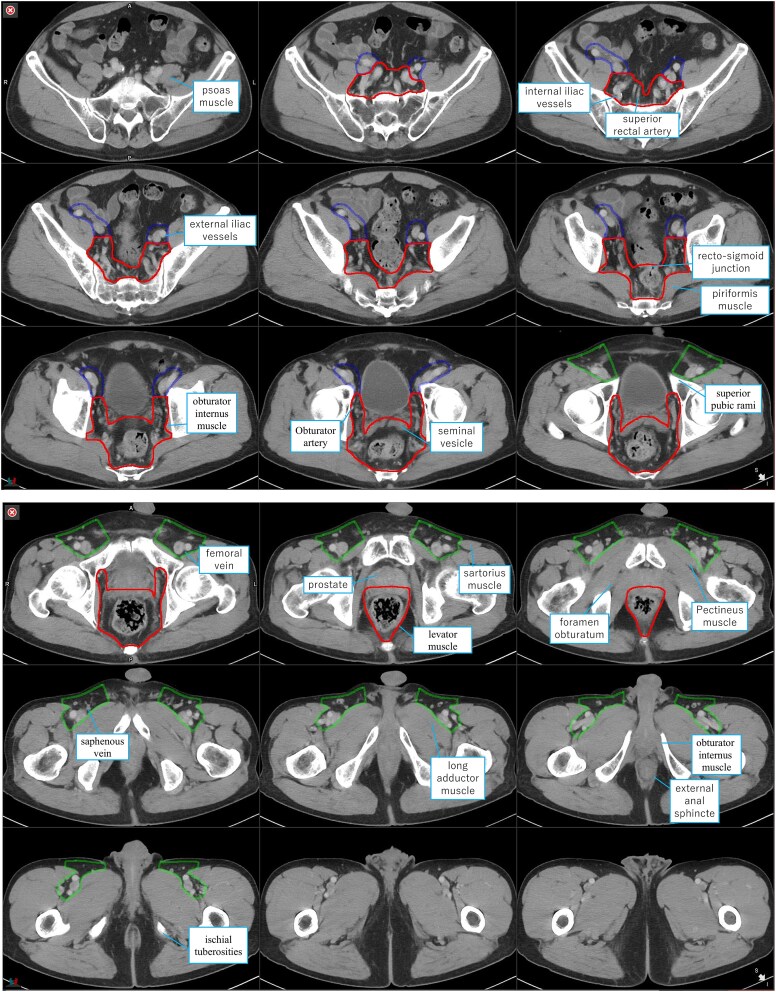

In the last decade, the role of radiotherapy in rectal cancer has changed significantly with the introduction of total neoadjuvant therapy (TNT) and nonoperative management (NOM). For the setting of irradiation field in rectal cancer, the pararectal, lateral lymph nodes, and those along the inferior mesenteric artery (IMA) are most important. In total mesorectal excision (TME), the root of the IMA is dissected. In the atlas of pelvic irradiation for rectal cancer, the setting of the upper margin of the mesorectum varies from atlas to atlas, and no atlas sets the upper margin of the mesorectum to the root of the IMA. In particular, there is no consensus on the definition of anatomical boundaries regarding the lymph nodes along the superior rectal artery (SRA). The upper margin of the irradiation field in clinical trials of preoperative radiotherapy and TNT is generally set at the level of the internal and external iliac artery branches, L5/S1, or S2/S3. However, it is not necessary to include the entire mesorectum to the root of the IMA in patients undergoing preoperative radiotherapy plus TME. Conversely, for patients receiving NOM, the irradiation field may have to include the mesorectum to the IMA root, though the incidence of lymph node metastasis and gastrointestinal adverse events merits consideration. It is increasingly important to determine the extent of clinical target volume around the SRA region and the setting of the upper margin of the irradiation field after formulating the treatment policy together with the surgeons and medical oncologists.